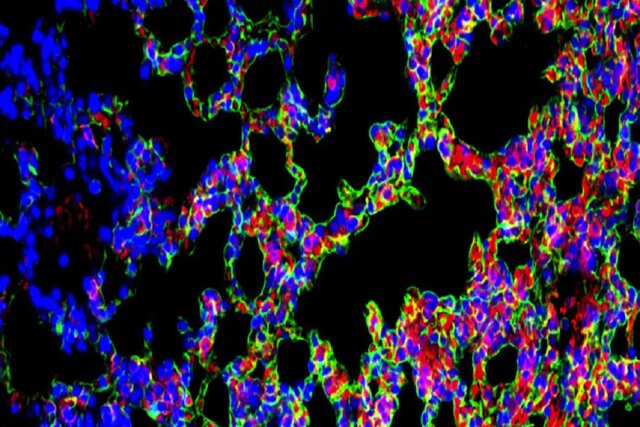

مشخص نیست که چه چیزی فیبروز ریوی ایدیوپاتیک را ایجاد می‌کند اما پیشروی بافت زخم، در نتیجه فعالیت غیرعادی سلول‌های اپیتلیال در ریه‌ها رخ می‌دهد. این سلول‌ها که مانند یک رابط میان محیط و بدن عمل می‌کنند، در آغاز واکنش‌های ایمنی دخیل هستند و به ترمیم زخم کمک می‌کنند.

در بیماران مبتلا به فیبروز ریوی ایدیوپاتیک، سلول‌ها آسیب می‌بینند و تولید مقادیر زیادی از کلاژن و پروتئین‌های خارج سلولی را آغاز می‌کنند که به ایجاد زخم در ریه‌ها منجر می‌شوند. یک راهبرد درمانی موثر مستلزم آن است که هم ماتریس خارج سلولی اضافی پاک شود و هم سلول‌های اپیتلیال آسیب‌دیده به حالت سالم بازگردانده شوند.